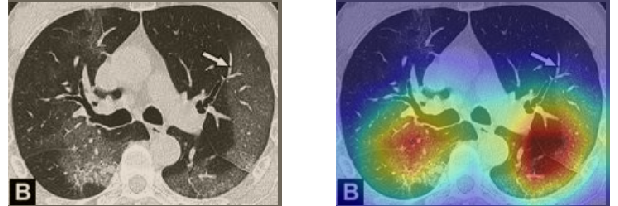

In order to make our models more transparent and provide detailed visual analysis, we present the Grad-CAM localization maps obtained by different models. We consider CT images with COVID-19 abnormalities from the test set of each dataset and highlight the important regions considered for the prediction. For the SARS-CoV-2 dataset we use the Inception V3 model. Figure 13 shows the original CT images and their localization maps. Our model is capable to detect regions that show abnormalities in the CT scans.

In a similar way, we consider classifying the test CT scans from the COVID-19 dataset by the DenseNet169 model and highlight the important regions considered for predictions. We present the original CT images and their localization maps in Figure 13. We can also see that our model is capable to detect the COVID-19 related regions as marked (small square in some images) by expert radiologists.

A wide variety of typical and atypical CT abnormalities have been reported for COVID-19 patients in various studies [58, 59]. So, we tested our models on external CT images extracted from these two publications as they feature typical findings of COVID-19 pneumonia marked by specialists. In order to make sure that not any of the extracted images are unintentionally included in our datasets, specifically the COVID19-CT dataset, we use the model trained on the SARS-CoV-2 dataset. First, the InceptionV3 model is employed to classify the extracted CT images. The model is able to correctly classify the given CT images as COVID-19. Second, in order to interpret the model’s generalization capabilities, we apply the Grad-CAM technique to visualize the regions of abnormalities that are considered. By assessing the different CT images in Figure 15, we can see that the model accurately localizes the disease-related regions. Even more interesting is the fact that the model ignores any specific marks in the images like letters and only localizes the COVID-19 related regions. These visual explanations show the success of our models to learn relevant, generic visual features related to COVID-19 and are capable to correctly classify CT images outside the datasets on which they are trained.